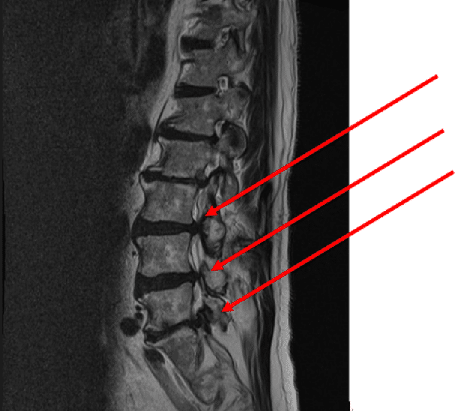

上の写真を見ると神経が圧迫を受けているのがわかります。

正常な腰のMRIで比較すると一目瞭然です。

背骨の後方にある脊髄に圧迫は見られません。

狭窄の結果、神経を圧迫して、脚の痛みやしびれ、腰痛を出すことをいいます。